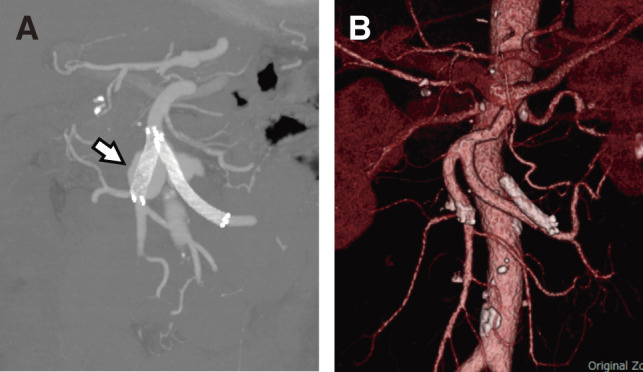

Superior mesenteric artery (SMA) aneurysm and their surgical interventions are rare, leading to infrequent reports of postoperative complications. This report describes 2 cases of refractory diarrhea following vascular reconstruction for infectious SMA aneurysms. Both patients underwent aneurysm resection and SMA reconstruction but experienced persistent diarrhea despite treatment with anti-diarrheal medications. Postoperative diarrhea, a complication observed after resection of the nerve plexus around the SMA in gastrointestinal surgery, may be attributed to intraoperative injury to the nerve plexus in our cases. Though palliative therapy is partially effective, more efficacious management strategies are desirable to address this persistent complication.